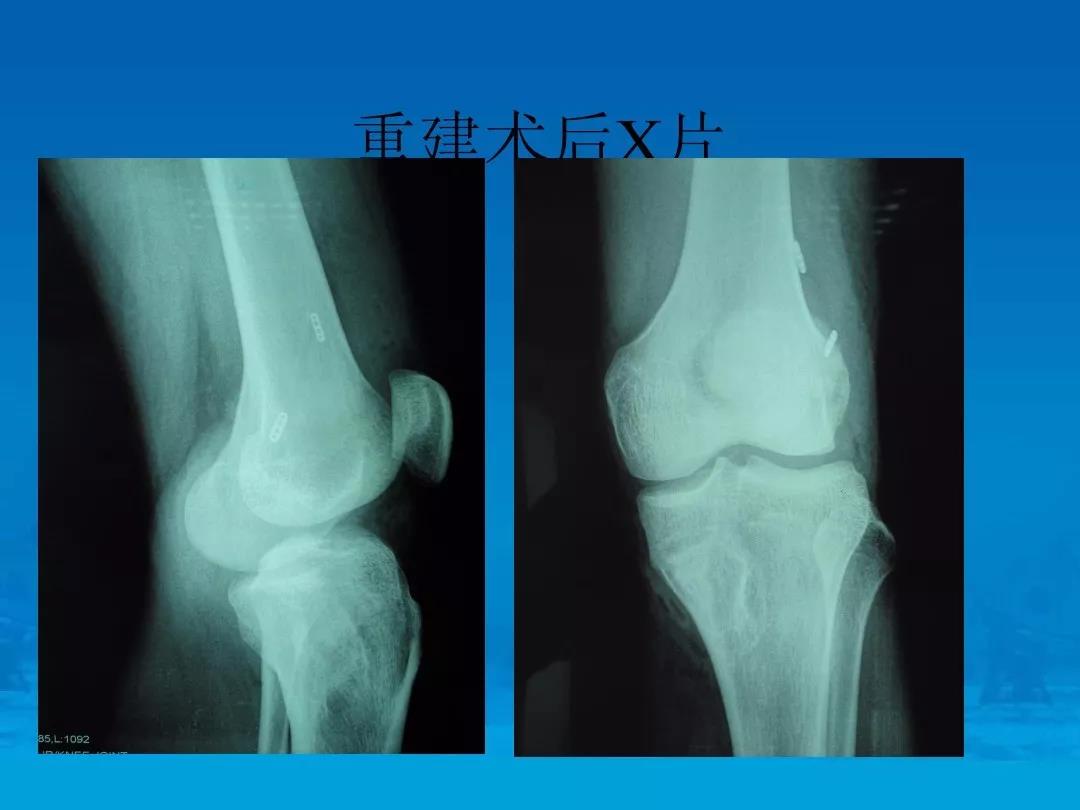

精选:关节镜下重建前交叉韧带